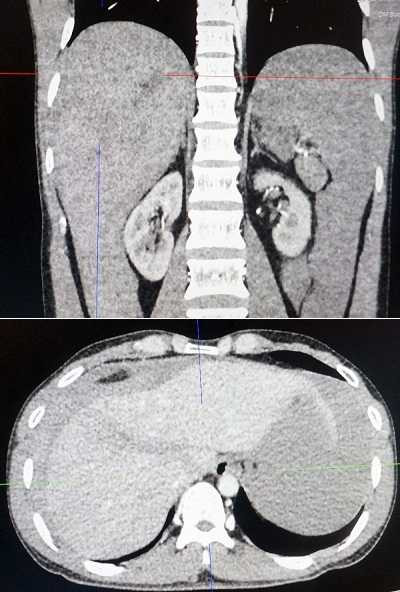

Hình ảnh trên phim chụp CT gan của bệnh nhân trước khi phẫu thuật.

Kết quả chụp CT 160 lát cắt cho thấy gan phải của bệnh nhân bị vỡ nát và ổ bụng có nhiều dịch, bệnh nhân được khẩn cấp chuyển lên phòng mổ. Tại đây, bệnh nhân được truyền máu liên tục, được sử dụng các loại thuốc đặc hiệu để ổn định tình trạng bệnh, sẵn sàng cho ca phẫu thuật.